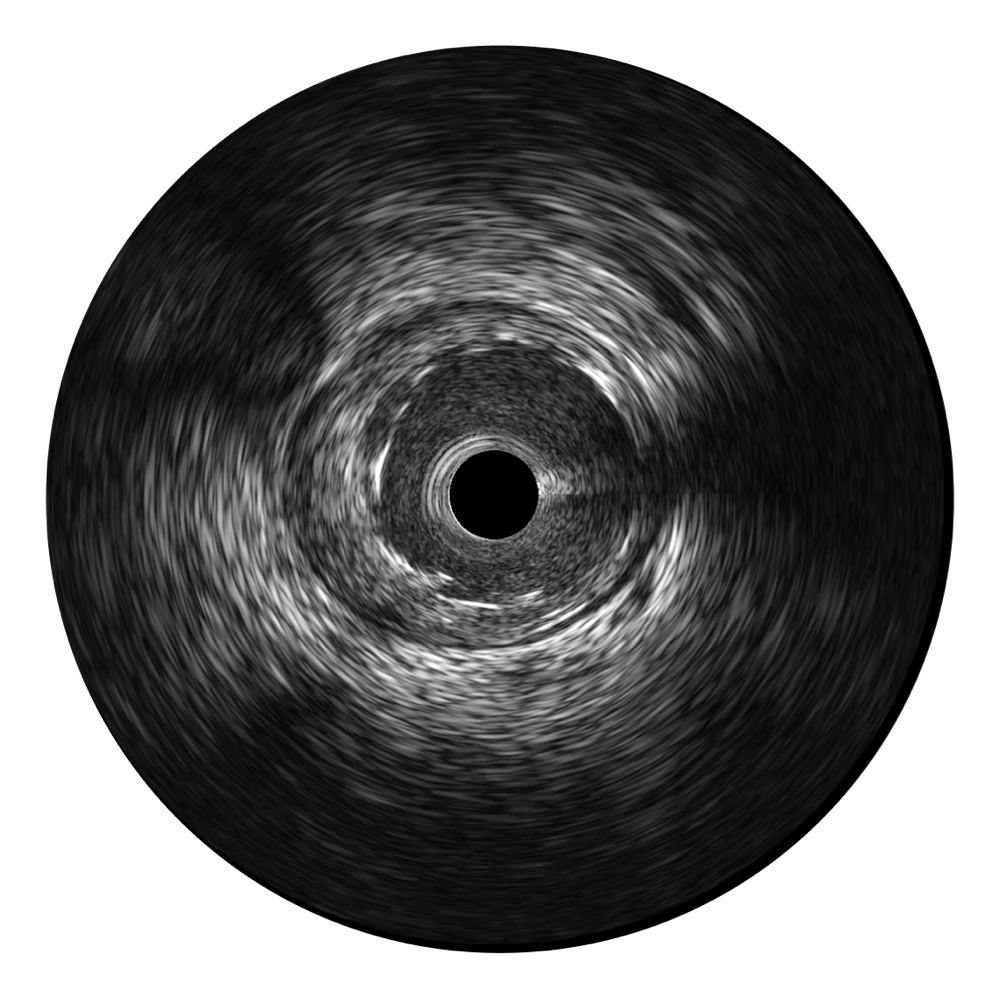

• 传统IVUS图像

对比传统IVUS导管成像,竞技宝(JJB)官方网站宽频IVUS图像的近场支架梁显影更细腻,远场中膜外血管仍清晰可辨,兼顾远中近,兼顾分辨力与穿透深度